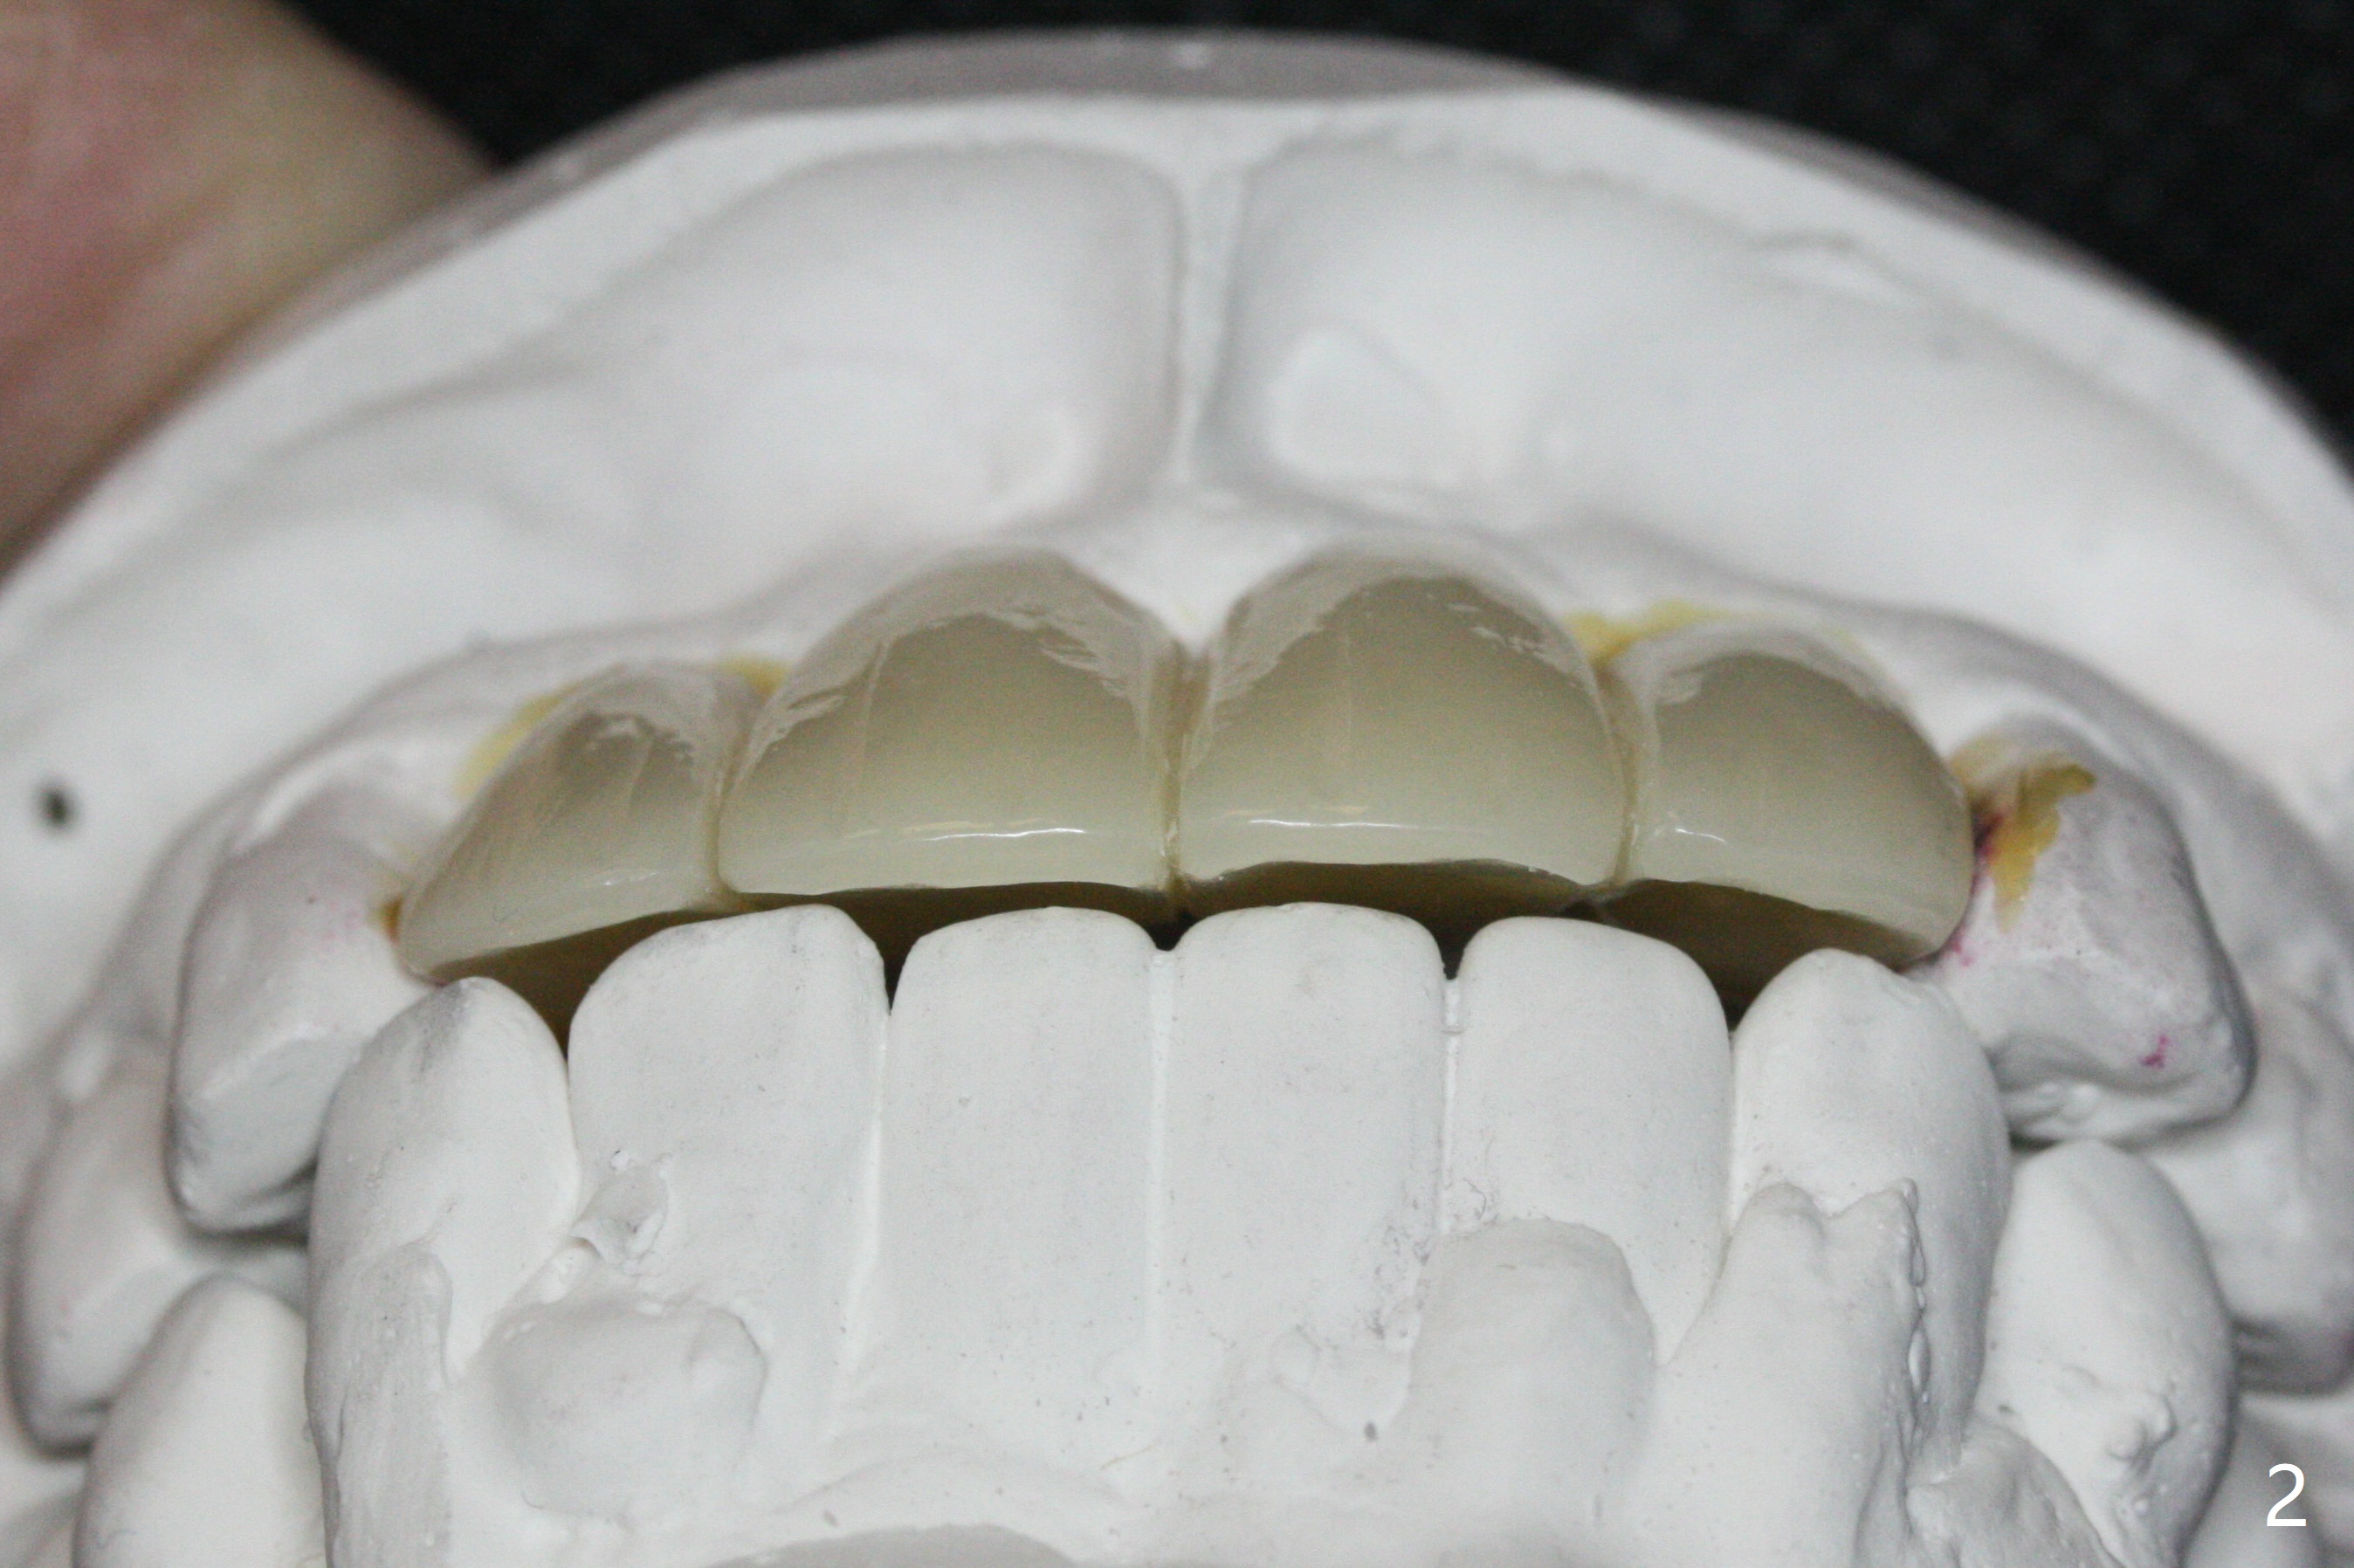

Although the ridge of the maxillary anterior ridge looks moderate in width (Fig.1), the bone is ~4 mm buccopalatally. Suction down surgical stent (Fig.2') made from the lab-fabricated provisional (Fig.2) will be used to check the position and trajectory of osteotomies. PAs taken after initial osteotomies (1.2 mm drill) show those at the central incisors tend to be mesial (close to the Incisive Canal *), while those at the lateral incisor sites distal (Fig.3,4). After adjustment, the position and trajectory of the osteotomies are acceptable (Fig.5,6). To reduce the chance of perforating the Incisive Canal (Fig.3,4 *), 2.5 mm 1-piece implants are inserted with >40 Ncm (Fig.7,8). After deep placement of the implants, Vanilla graft is placed at the crest (Fig.9,10 *). An immediate splinted provisional is fabricated from the suction down stent. The gingiva is healthy around the provisional (Fig.11) and the implants (Fig.12,13) 1 month postop. The provisional is adjusted monthly so that the interdental papillae can be elongated. No bone resorption is observed 6 months postop (Fig.14,15). Crowns are cemented 8 months postop (Fig.16-18). The keratinized gingiva appears to have formed the abutments 8 months postop immediately pre-cementation (Fig.19).